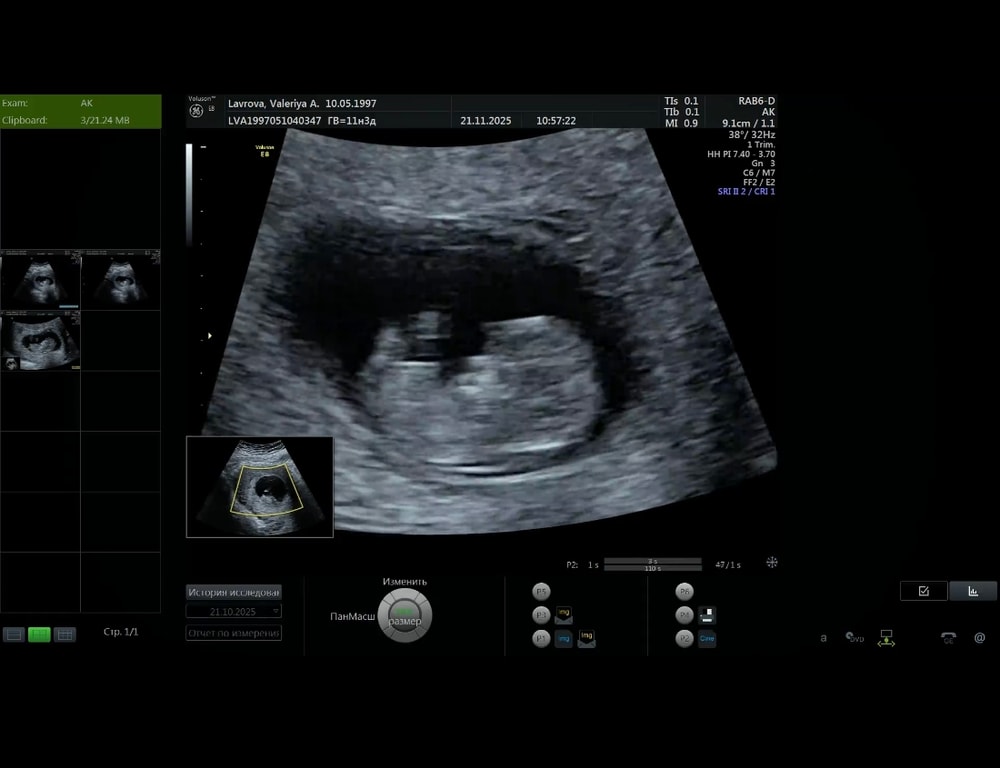

11,4 недельки

Про хорошее. Была сегодня на узи) скрининг на след неделе, но там ниче не покажут, как обычно, потому мне захотелось заранее сходить и глянуть на свою кроху))). У малышка все замечательно, брыкается уже во всю, чсс 168, нарадоваться не могу 🤗🤞